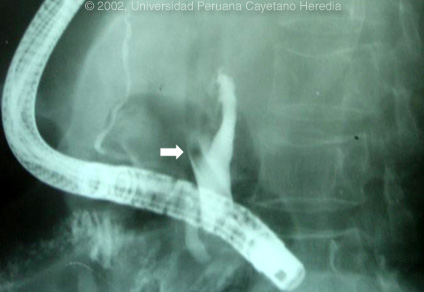

Epidemiology: Impoverished urban dweller. No TB exposure. No ethanol history. No ill contacts. Physical Examination: Afebrile. Acutely tender abdomen predominantly in the epigastric area but without peritoneal signs. Normal rectal exam. Labs/X-ray: Hematocrit 42. WBC 12,200 with 70 segs, 10 bands, 5 monos, 13, lymphs and 2 eos. Amylase 500 (N=40). Bilirubin 1.8, direct predominance. SGOT 2X normal. Normal BUN and creatinine. Abdominal CT was read as compatible with acute resolving pancreatitis. An ERCP was performed and after papillotomy dye injected into the common bile duct; the arrow on the image demonstrates the relevant filling defect.

| Diagnosis: Pancreatitis and acute biliary obstruction due to Ascaris lumbricoides. |

| Discussion: The lengthy dye-free filling defect (shown by the arrow in previous image; also shown again at bottom of this page) obstructing one of the main hepatic ducts, and which had extended back through the papilla of Vater, corresponds to the shape of an adult Ascaris lumbricoides that had aberrantly migrated into the biliary system from its normal home in the intestinal lumen. The images below show direct endoscopic visualization of the tail end of the adult worm sticking out of the common bile duct after the endoscopic papillotomy. In real time the worm can be seen moving back and forth as it migrates up the biliary tree. Through a wider papillotomy the tail end of the worm was grabbed with the forceps as shown in the digital image and physically removed, thus obviating the need for laparotomy in this case. The final image shows the common bile duct opening after the worm was removed.